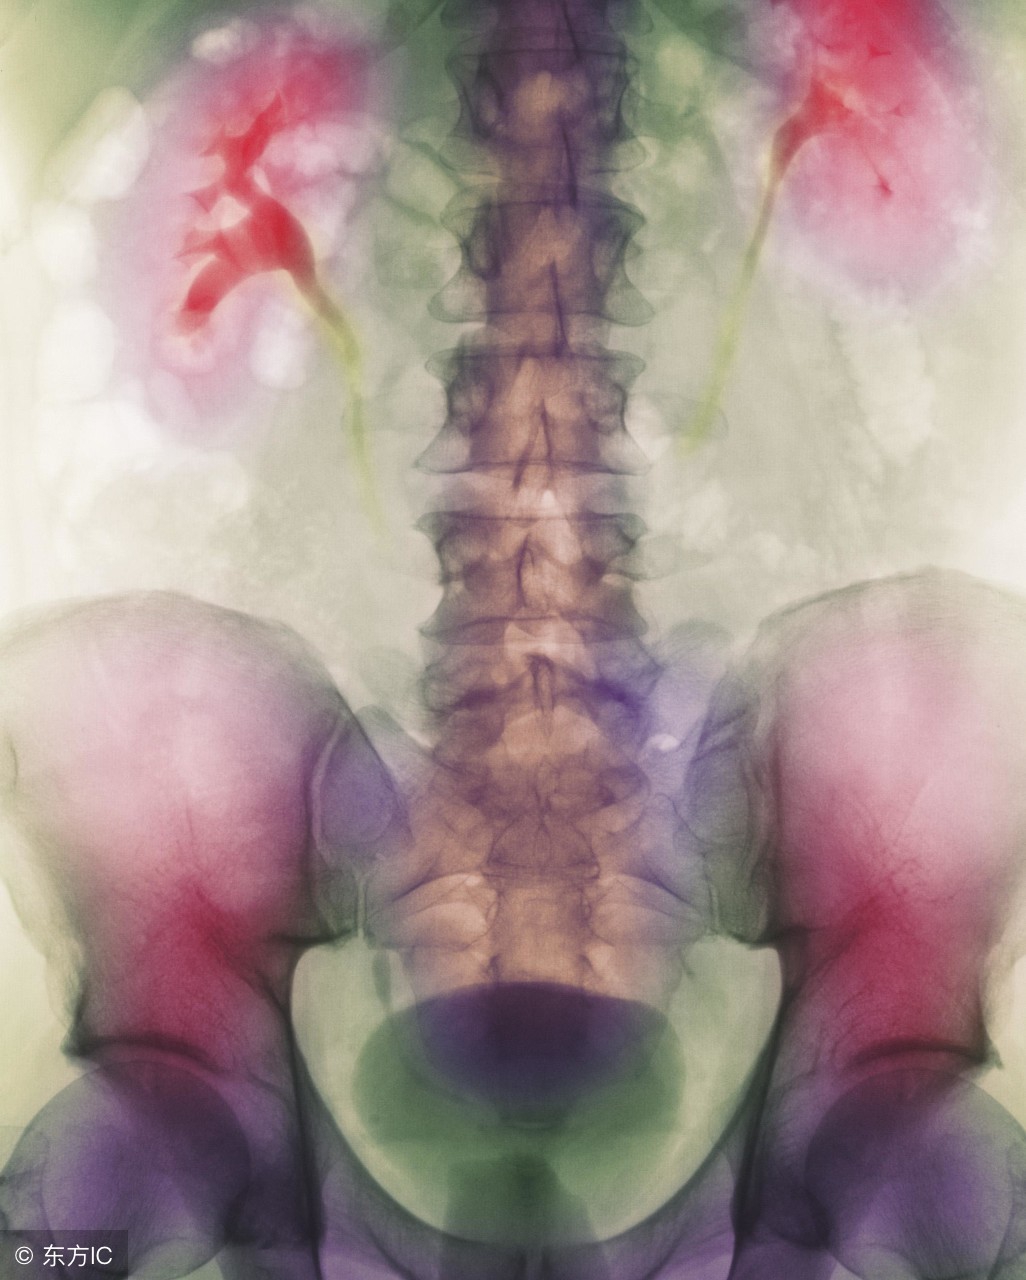

尿结石的检查

后尿结石可经直肠指检触及,前尿结石可直接沿尿道体表处扪及,用尿道探条经尿道探查时可有摩擦音及碰击感。X线平片可明确结石部位、大小及数目。尿道造影更能明确结石与尿道的关系,尤其对尿道憩室内的结石诊断更有帮助。